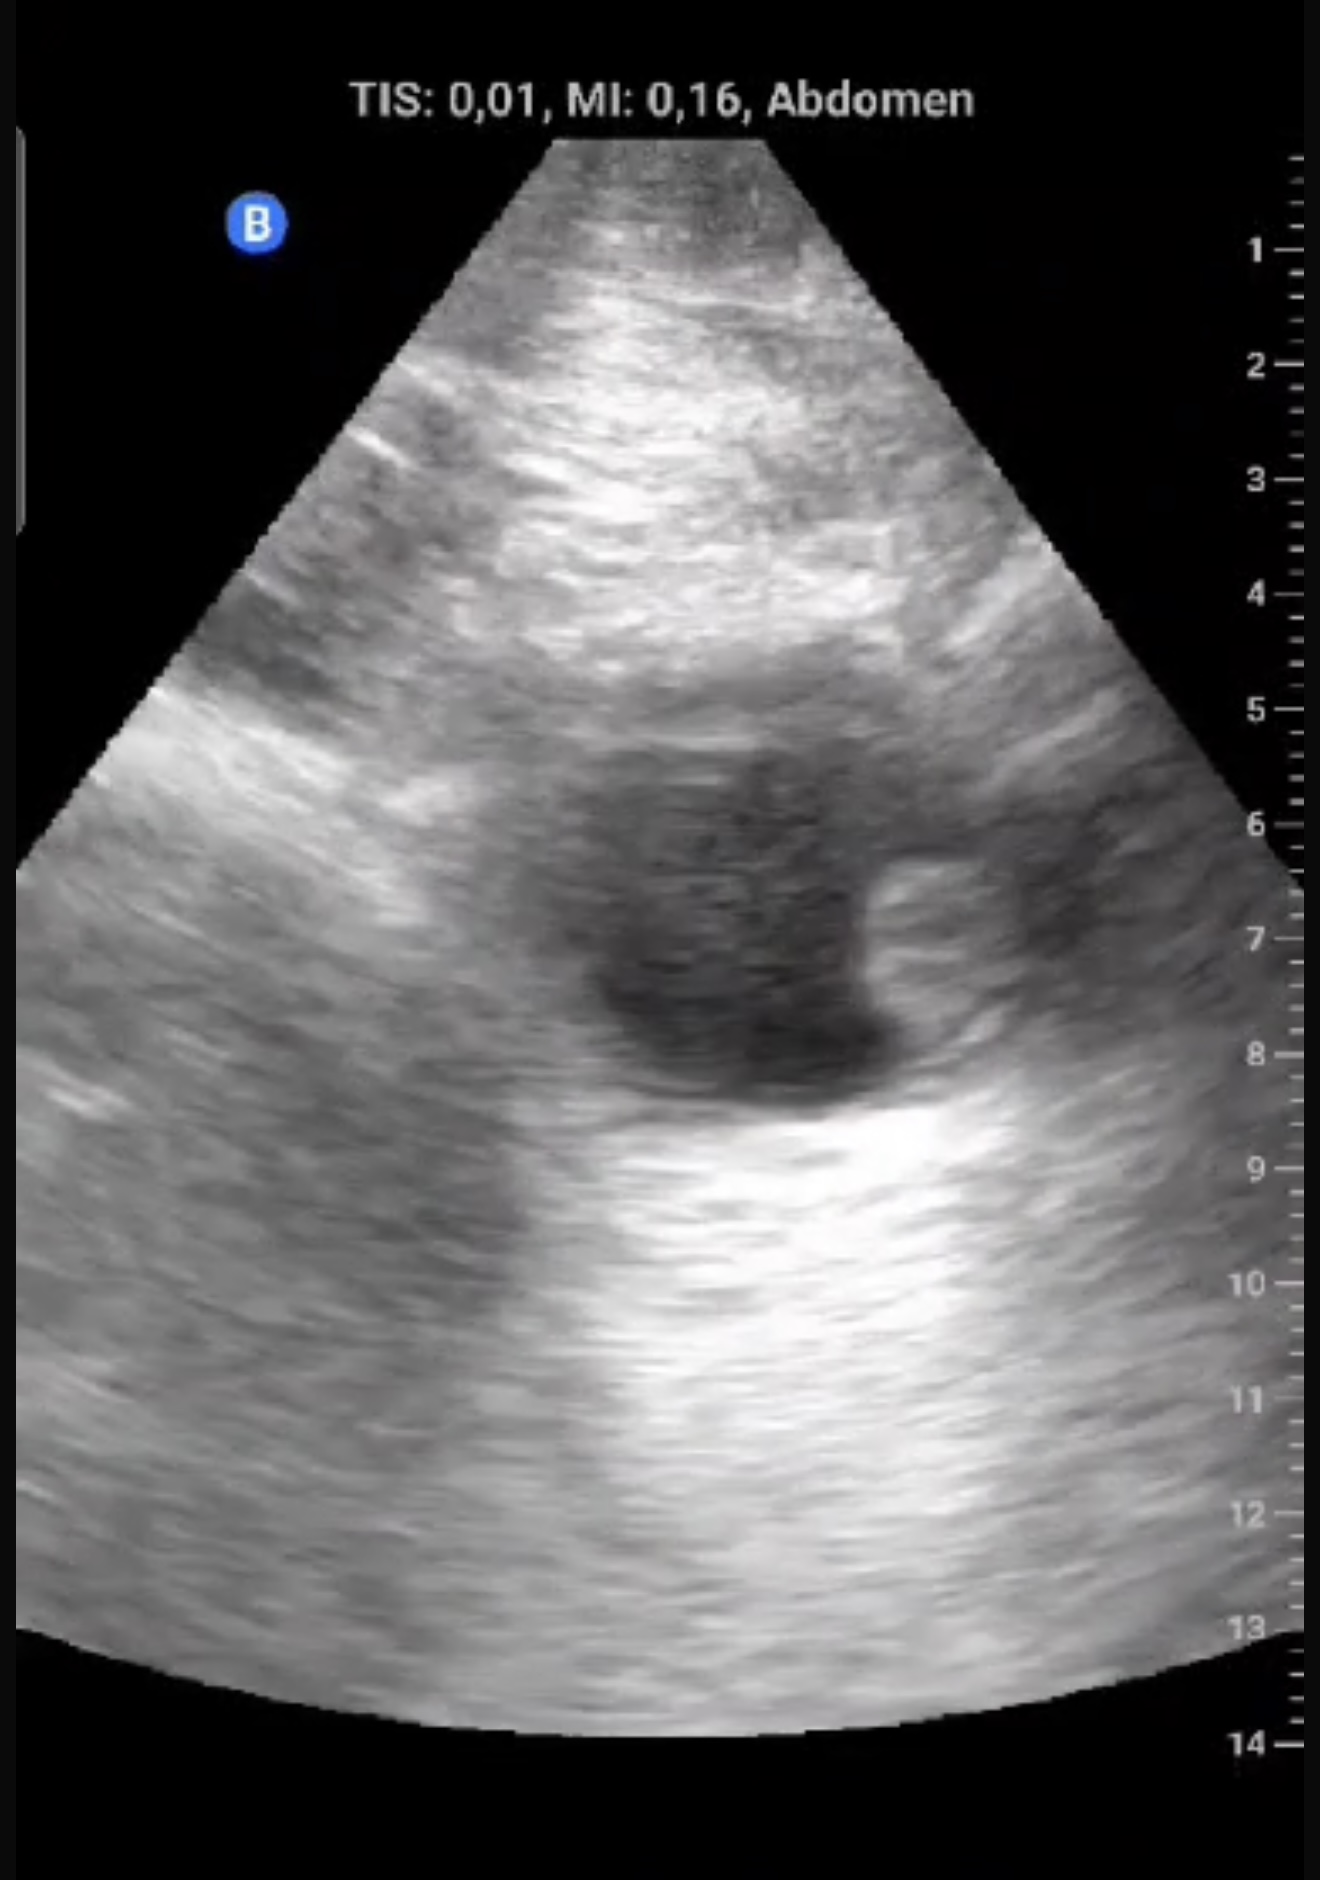

Exfumador, HTA, hipercolesterolemia, cirrosis hepática por alcohol. Hombre de 58 años que refiere episodio de hematuria macroscópica hace dos semanas, coincidiendo con un esfuerzo físico intenso el día previo. No presenta disuria, fiebre, poliaquiuria, ni dolor. En controles posteriores, no había recurrencia de hematuria y el paciente se encontraba asintomático.Exploración física sin hallazgos relevantes. Ecografía realizada en consulta en apenas 5 minutos mostró una masa en la cara lateral izquierda de la vejiga, de 1,5 x 1,3 cm, con características sugerentes de lesión tumoral superficial.

Lesión sólida, pediculada, de bordes definidos y fronda larga en la cara lateral izquierda de la vejiga.

Se sospechó un tumor vesical; pólipo vesical. Urología confirmó la lesión mediante cistoscopia, describiendo una masa papilar superficial de 2 cm en la pared lateral izquierda.